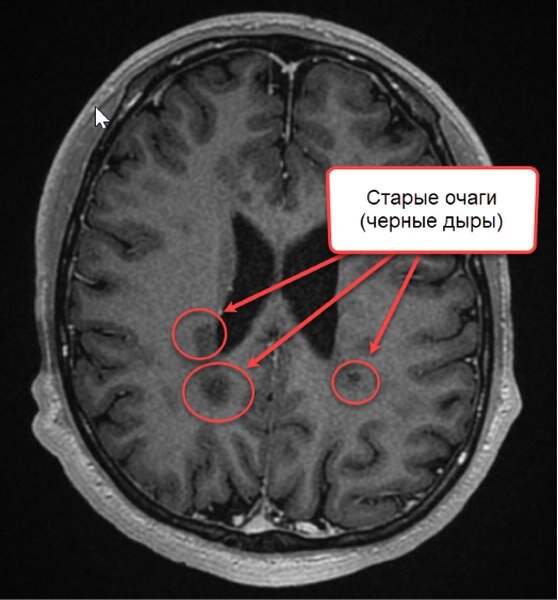

При рассеянном склерозе дают инвалидность